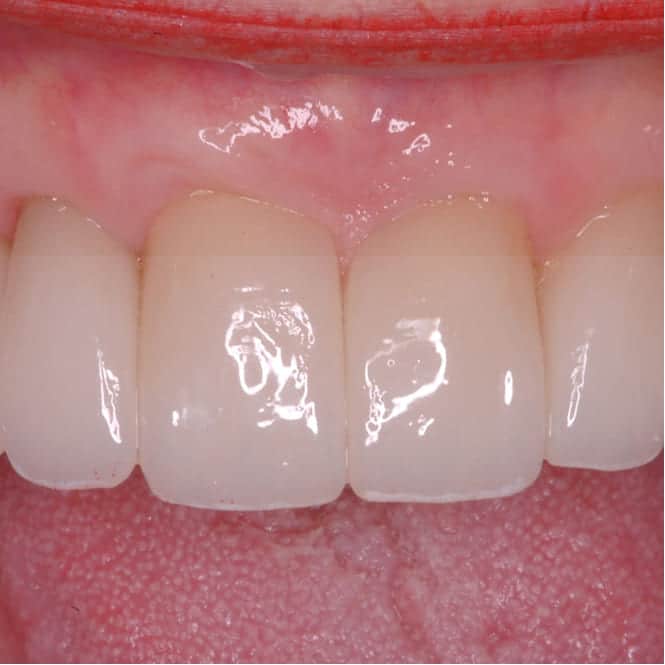

After treatment showing restored periodontal health with even gum contours and improved smile aesthetics After

The change in RW's mouth was substantial. Recession defects were covered, fibrotic tissue was reshaped, and the gingival margins were even and properly contoured for the first time in years.

The restorative work that followed blended naturally with the improved soft tissue architecture, producing an aesthetic result that would not have been achievable without first addressing the periodontal foundation.

RW reported that the process changed how he thought about dental care. He committed to regular maintenance and proper home care — not because he was told to, but because he had seen firsthand what the foundation actually does for the result.